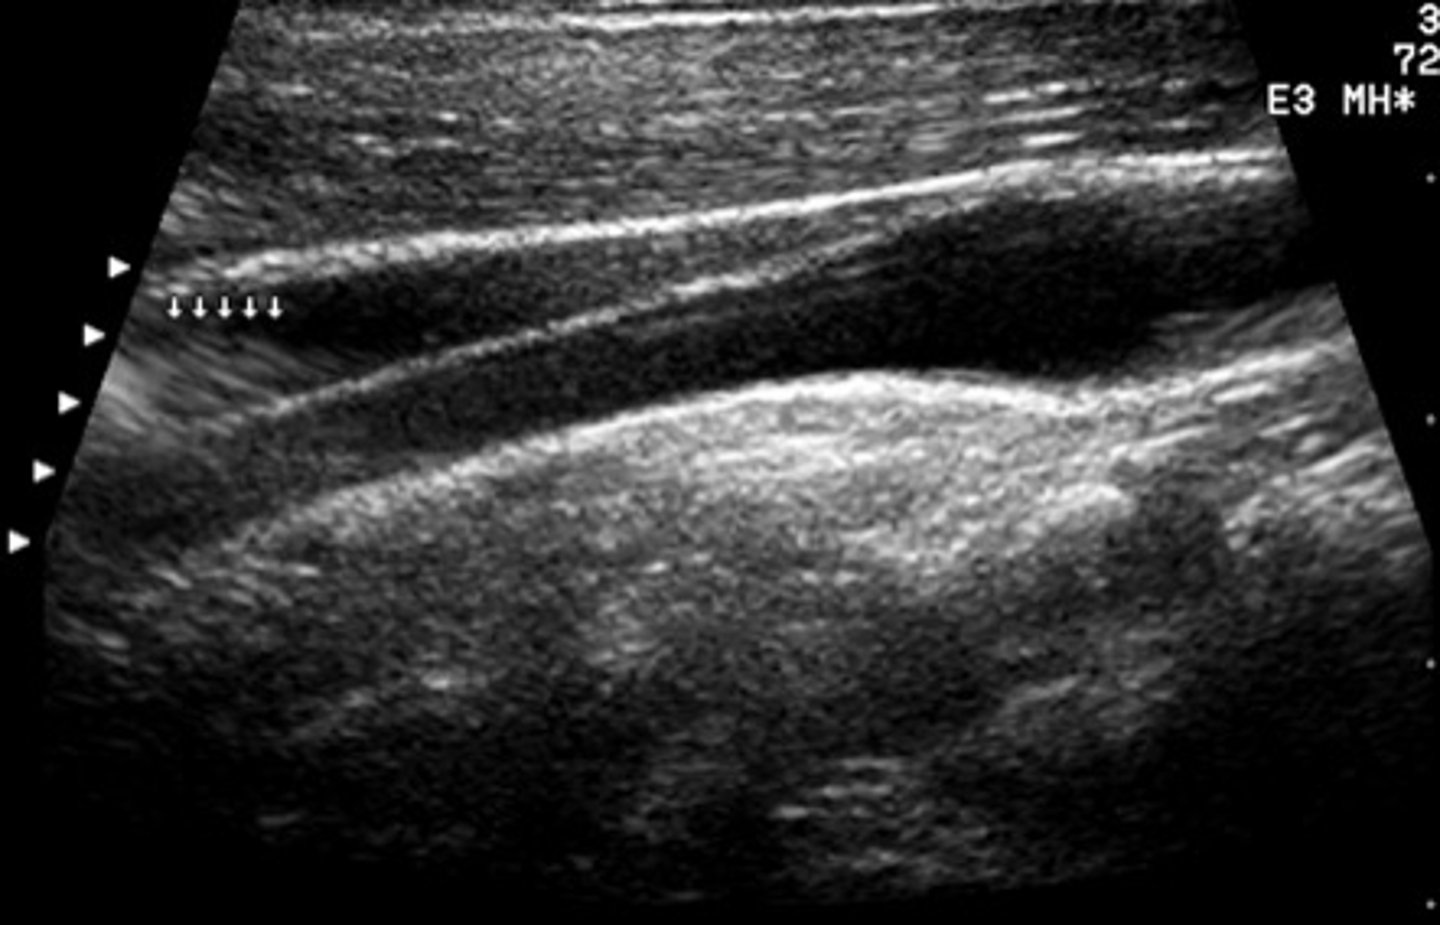

This image was displayed with a linear array transducer that employs phasing to steer the beam. What artifact do the arrows point to?

grating lobes

<p>grating lobes</p>